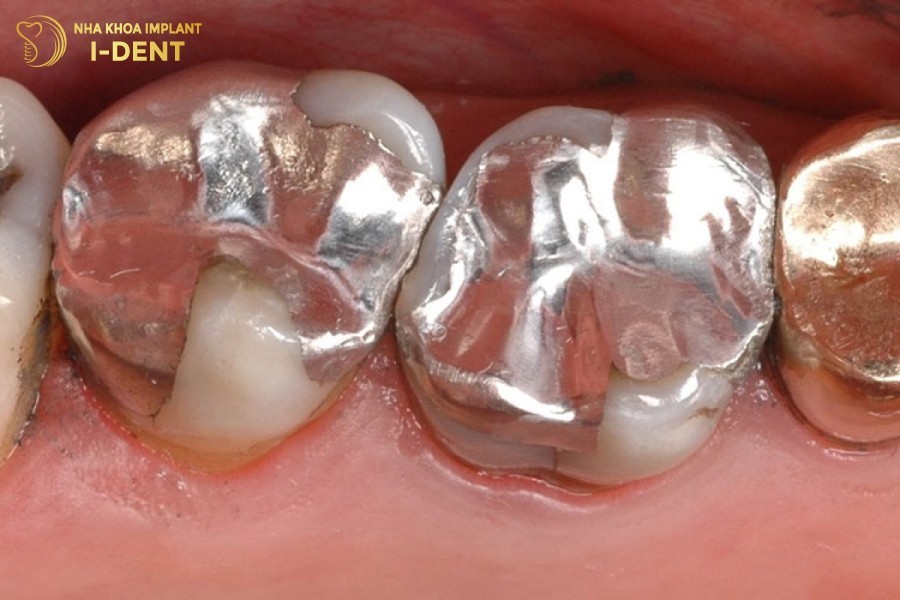

2.4 Gây nguy hại cho sức khỏe

Tác hại của việc trám răng sai cách có thể ảnh hưởng đến cả sức khỏe cơ thể. Trong đó, dị ứng vật liệu trám răng là một tác hại nguy hiểm. Bên cạnh những vật liệu được kiểm định an toàn và có độ bền cao thì vẫn có những vật liệu giá rẻ, không đảm bảo chất lượng. Đặc biệt là Amalgam, vật liệu có nguồn gốc từ thủy ngân khi sử dụng có thể gây hại cho sức khỏe. Những người cơ địa nhạy cảm có thể nhiễm độc thủy ngân.

Amalgam là vật liệu trám răng có chứa thủy ngân